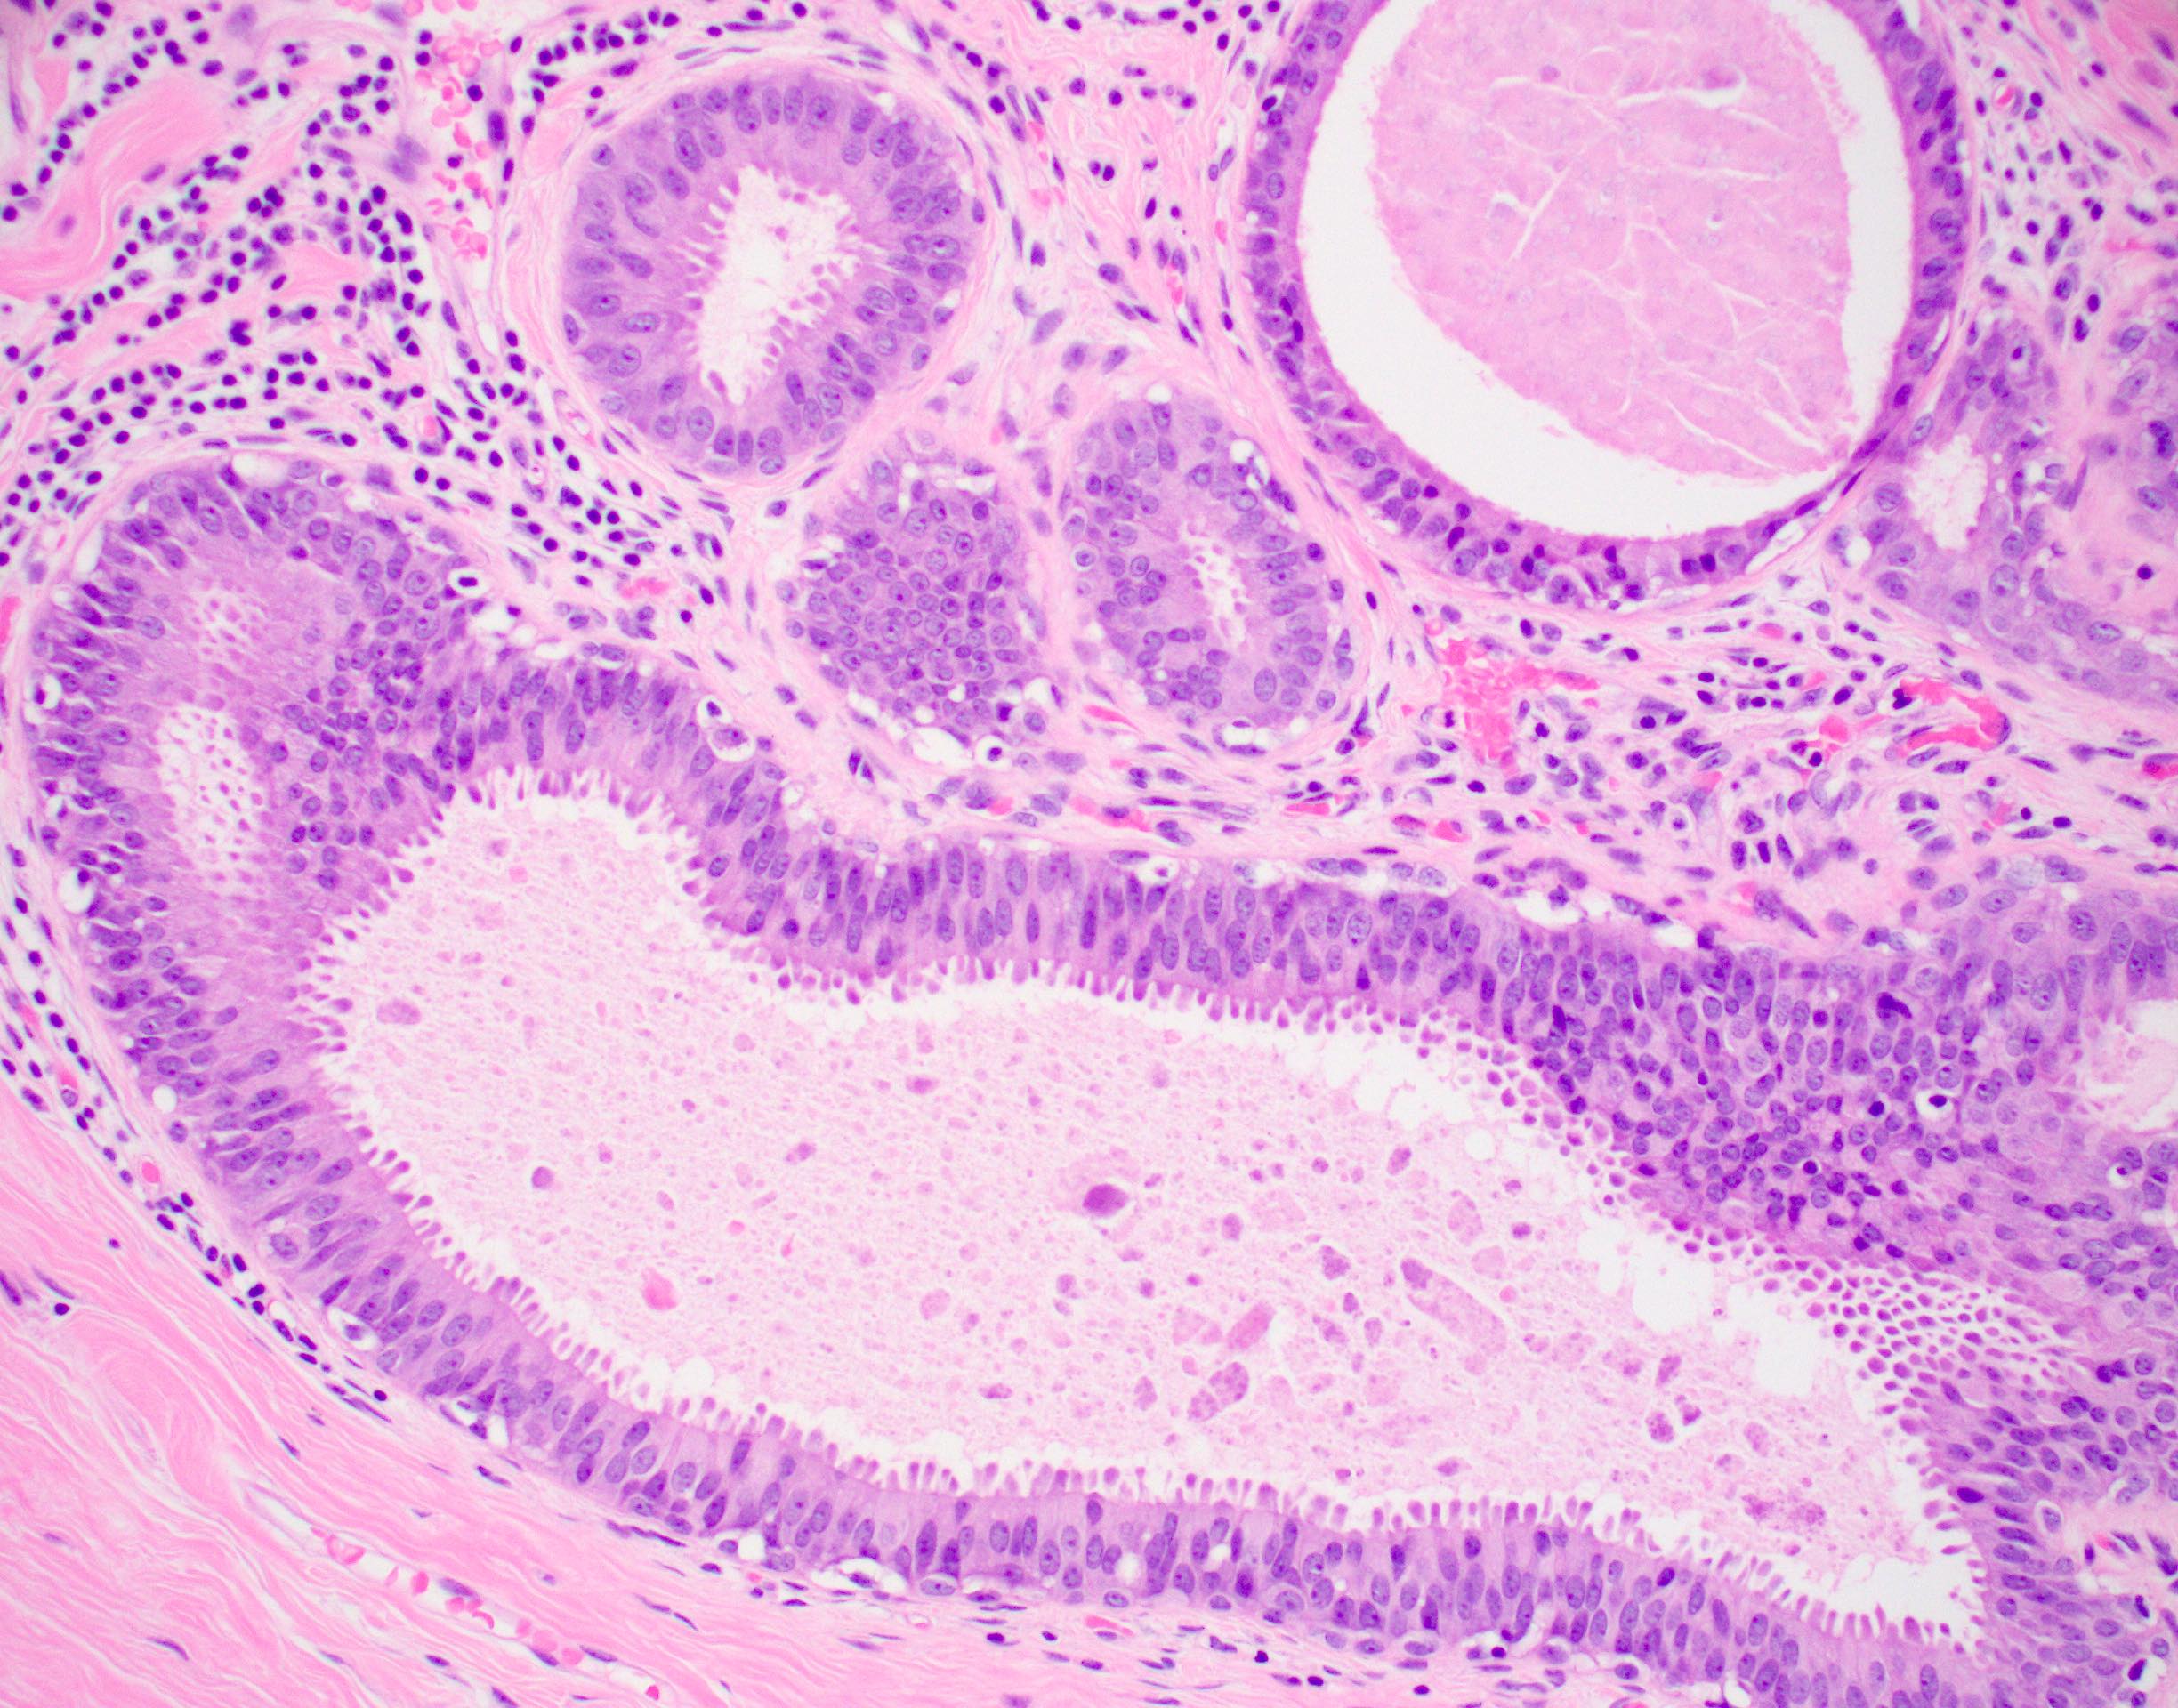

Гистологические изображения фолликулярной кисты яичника